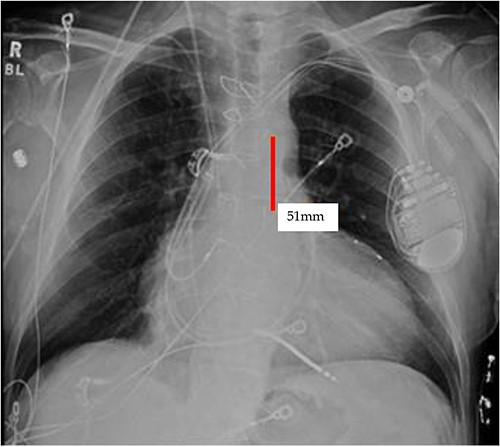

TEE guidance and fluoroscopy were used during the insertion of this patient’s left axillary IABP. The TEE note post-IABP insertion states that ‘the balloon is seen from the distal end of the aortic arch extending into the descending aorta.’ A same-day post-insertion CXR in the ICU showed a shortened IABP at about 5.1 cm long, indicating that the balloon must have been folded over itself to allow both markers to be so close to each other (Fig. 4).

Initial CXR: note the proximal and distal radiopaque markers of the IABP are visualized a few centimeters (5.1 cm) from each other; the proximity of the two markers indicates that along the path of the IABP, it has folded over itself causing the two markers to be abnormally close, as the 8Fr. balloon is 258 mm long, thus the markers should be separated by that much.

It appears that the IABP became mispositioned after its initial placement as seen on follow-up CXR (Fig. 4). Despite almost daily CXRs, this IABP mispositioning was missed by the managing team and radiologists, probably due to interference from the automatic implantable cardioverter defibrillator (AICD) leads, EKG leads, and sternal wires. Twenty-one days later (Fig. 5), the radiologist erroneously read that the IABP had been removed, so CXRs were never repeated. Figure 5 shows that the IABP was still folded over itself but now with a shadow in the arch/ascending aorta from the migrated IABP.